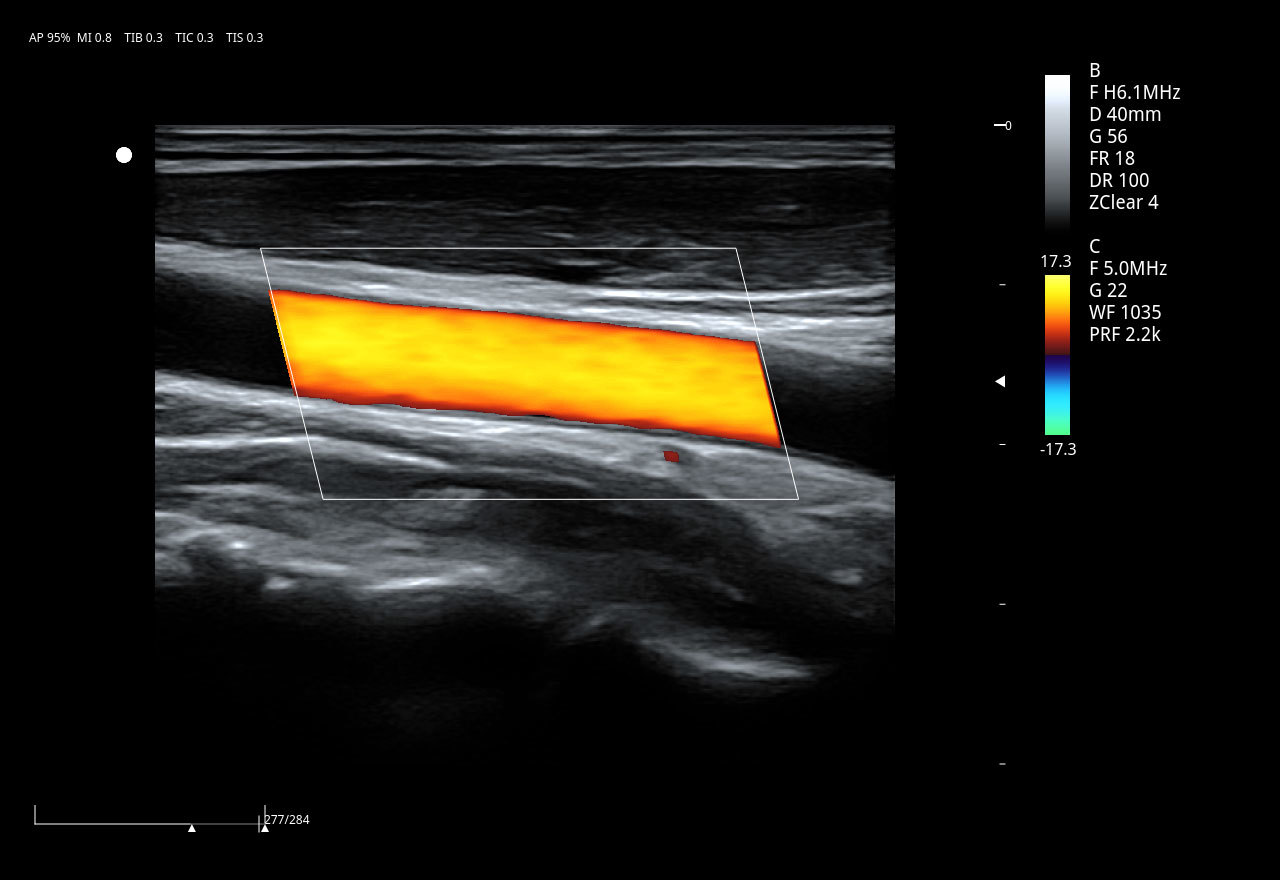

Линейный датчик 7L4PD

• Рабочая полоса частот: 4,2–15,0 МГц

• Количество элементов: 128

• Апертура: 38 мм

• Применение: сосуды (в т.ч. сонные артерии), поверхностные органы (ЩЖ, молочные железы), периферические нервы, MSK, ортопедия, яички, лёгочная диагностика, педиатрическая абдоминальная диагностика.

2. Сосудистые исследования